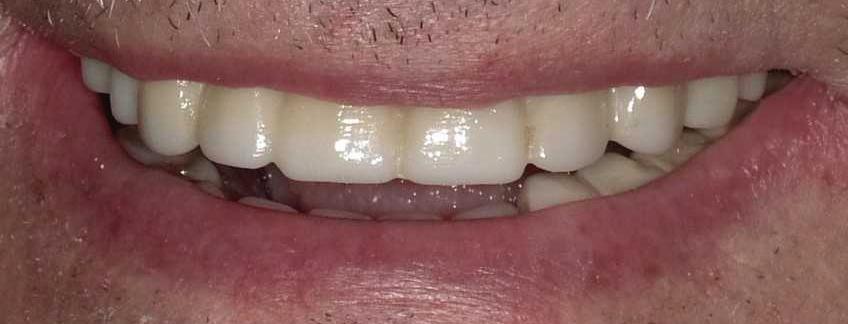

Submitted By Sivakumar Sreenivasan, DMD, MDS Dental Implant Center of Rockville

Can just four implants replace all of the teeth on the top or the bottom of your mouth? Thanks to advances in dental implant technology, that answer is a resounding yes.

Believe it or not, tooth loss is extremely common among adults, especially as we age. In fact, more than 35 million people in America are missing all of their upper and/or lower teeth. Rather than living with the discomfort and hassles of dentures, many people are opting for what is called “all-onfour” dental implant restoration.

All-On-Four:

One Full Arch Of Teeth, Four Dental Implants

To fully understand this remark-

A Reason To Smile Again All-On-Four

able technique for replacing teeth, you should first understand what a dental implant is. An implant is a small titanium screw that fits inside your jawbone and replaces the root-part of a missing tooth. Minor surgery is required to insert the implants. Once the implant is in place, a crown is attached to give you a highly realistic-looking and functional prosthetic tooth.

Here’s where it gets really interesting: You do not need a dental implant for each and every one of your missing teeth. All you need is four precisely placed implants on the top of your mouth, and four on the bottom, to restore your full smile. That’s the beauty of the all-on-four. And because the implant is made of titanium, it has the unique ability to fuse to living bone and function as part of it. So eventually, the dental implant becomes part of the jawbone and serves as a strong, long-lasting foundation for your new teeth.

What’s The All-On-Four Dental Implant Procedure Like?

It can be scary to get implants for the first time. Most of that fear is probably due to the uncertainty, so here is the step-by-step process for getting an All-On-Four dental implant.

First, your dentist will want to make sure your comfortable, so either local or general anesthesia will be administered.

Second, the dentist or surgeon will prepare your mouth for the implants, which involves removing your remaining teeth that are failing. They will then remove any diseased or infected tissue from your jaw and gums.

Besides ensuring that your implants are permanently fixed in place, this bone fusion has another important benefit: it prevents future bone loss in the jaw. This helps to maintain a more youthful facial structure – and better oral health. But perhaps the biggest surprise about the all-on-four is how quickly it can transform your life.

After the implants have been placed, they will thoroughly clean the surgical sites and suturing all the incisions. Then you’ll be taken to a recovery room where you can relax and take time to wake up from the anesthesia.

How Do You Know If The All-On-Four Procedure Is The Right Option For You?

At your All-On-Four consultation, you’ll receive a 3D CT Scan. This scan will help determine if you need implants and assist your doctors in creating your treatment plan. So if you want to learn more about dental implants, simply schedule a consultation with an All-On-Four provider. It’s the best way to find out how dental implants can change your life.

Next, they will begin the implantation process. This means they will insert the titanium screws into your jawbone. Most likely, they will place two implants toward the front of your mouth and two towards the back of your mouth so the “anchors” can evenly bare the force of the denture.

301-805-6805 16 | Your HEALTH Magazine All-On-4: Same Day Smiles CALL TODAY TO GET YOUR OLD SMILE BACK! 301.294.8700 Dental Implant Center of Rockville 77 South Washington Street, Suite #205 Rockville, MD 20850 • www.DrSreeni.com Courtesy 3D Planning For Implants When patients bring a 3D scan with them to or have one taken in the office. Appointment needs to be scheduled before May 15, 2024 Missing Teeth or Tired of Wearing Dentures? Thanks to advances in dental implant technology, just four implants can replace all of the teeth on the top or the bottom of your mouth.